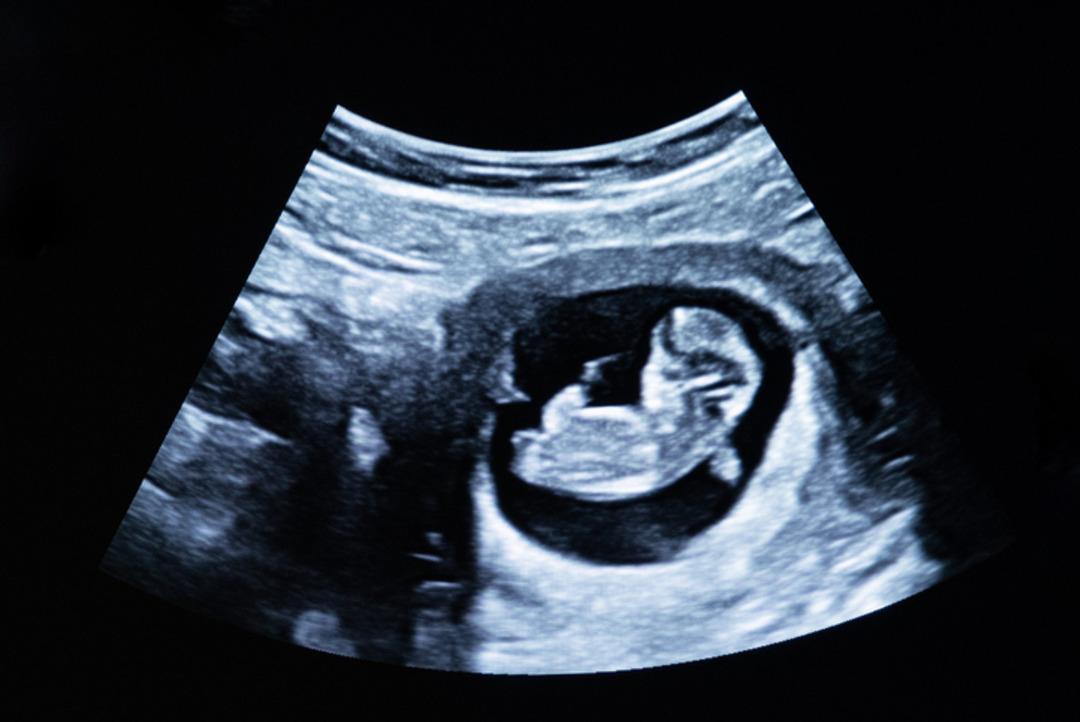

Hindistan'ın Uttar Pradesh eyaletinde yaşanan olay kan dondurdu. Hindistan’da yaşayan 30 yaşındaki Sarves isimli kadın karaciğerinde 12 haftalık bir bebek taşıdığı tespit edildi.

30 yaşındaki Sarvesh, aylardır yaşadığı şiddetli karın ağrısı, kusma ve yorgunluk şikayetleriyle doktora başvurdu. Kadın, antibiyotik verilerek eve gönderildi. Ancak şikayetleri artınca yapılan ileri tetkikler sonucu, Sarvesh’in karaciğerinde 12 haftalık olan bir fetüs tespit edildi.

Yaşadığı olayı BBC’ye anlatan kadın, "Sürekli kusuyor, yorgunluk ve ağrı hissediyordum. Ne olduğunu anlamakta zorlanıyordum" dedi. Bugüne kadar dünyada sadece 18 kişide görüldüğünü kaydetti.

Meerut'taki özel bir hastanede 90 dakika süren zorlu bir operasyonla fetüs çıkarıldı. Ameliyatta karnına çok sayıda dikiş atılan kadının ve iki çocuğunun bakımını eşi üstlendi.